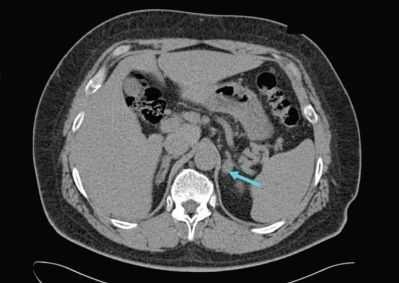

Диагностику надпочечниковой недостаточности начинают с оценки анамнеза, жалоб, физикальных данных, выяснения причины гипокортицизма. Проводят УЗИ надпочечников. О первичной надпочечниковой недостаточности туберкулезного генеза свидетельствует наличие кальцинатов или очагов туберкулеза в надпочечниках; при аутоиммунной природе гипокортицизма в крови присутствуют аутоантитела к надпочечниковому антигену21-гидроксилазе. Дополнительно для выявления причин первичной надпочечниковой недостаточности может потребоваться МРТ или КТ надпочечников. С целью установления причин вторичной недостаточности коры надпочечник КТ и МРТ головного мозга.

- КТ надпочечников. Рентгенологическая визуализация рекомендована для обнаружения кровоизлияний, очагов дистрофии и других патологических признаков, которыми проявляется первичная надпочечниковая недостаточность. Для оценки структуры гипофиза показана рентгенография турецкого седла, КТ головного мозга.